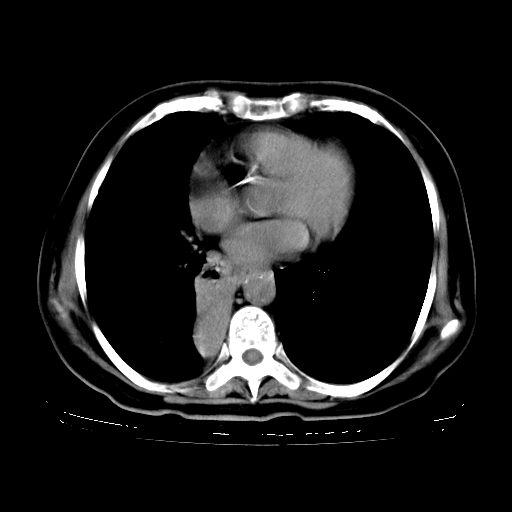

女,70岁,咳嗽、咳痰一个月,低热一周。

1.左上肺结核,部分纤维化。右肺中下叶部分肺不张,内见液化、坏死及点状钙化,右中下叶支气管壁增厚、管腔狭窄,见多个点状钙化,结合临床考虑支气管内膜结核,建议痰检查抗酸杆菌并参考血沉。两肺多个小圆点状高密度灶,境界模糊,多考虑结核肺内播散。但本人年龄较大首先应支气管镜检以除外右肺癌。

2.胸主动脉夹层。

1、右肺占位,考虑周围型ca 。

2、右下肺软组织密度肿块影,考虑肺隔离征。

3、两肺肺结核(右肺下叶背段及左肺)。

4、主动脉夹层。

5、右侧少量胸腔积液。

一元论:内膜结核伴下肺阻塞性肺炎并双肺播散!另:主动脉夹层。右侧少量胸腔积液。

支持,首先一元论解释。胸主动脉部分层面环形低密度,中心强化。环形影不强化。不象真假腔的改变。我考虑动脉炎,不太支持夹层动脉瘤-和大家的观点不一致,希望楼主让患者再做个心血管的彩超吧。